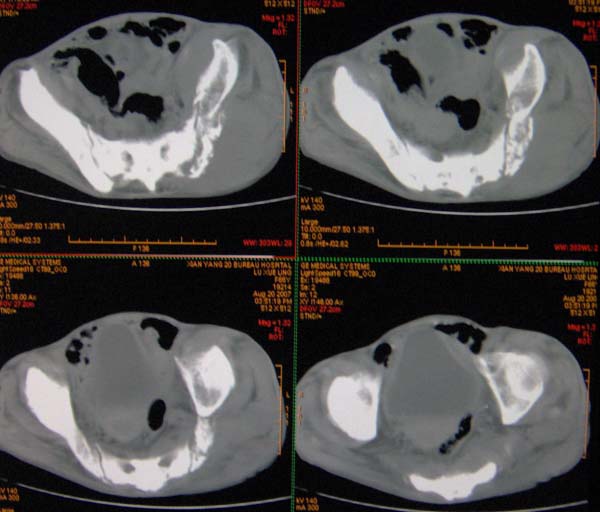

以下是引用ybing在2007-8-22 20:31:00的发言:[br]左侧髂骨溶骨样破坏;软组织肿块形成;其内未见肿瘤骨考虑纤维肉瘤或滑膜肉瘤不除外转移瘤

以下是引用qiushi在2007-8-22 21:39:00的发言:[br]双侧髂骨、骶骨侧快呈溶骨样骨质破坏,边缘模糊,左侧髂骨见骨折线,左侧髂部见软组织块影。考虑骨纤维肉瘤(中央型)伴病理性骨折,不排除骨髓瘤。建议本--周氏蛋白检查。[br] 鉴别点:[br] 骨纤维肉瘤,中央型者示边缘模糊的囊状溶骨破坏,一般无骨膜反映,可膨胀变形,突破骨皮质可形成软组织肿块,或并发病理性骨折。[br] 骨髓瘤,常表现为广泛的骨质疏松,皮质变薄或破坏,呈粟栗状、穿凿状、鼠咬状骨质破坏,边缘清晰,周围无硬化。[br] 骨转移瘤(溶骨型),表现为虫噬样、泡沫状圆形或卵圆形破坏区,很少出现软组织块影。[br][br][本贴已被 qiushi 于 2007-8-23 6:20:19 修改过]